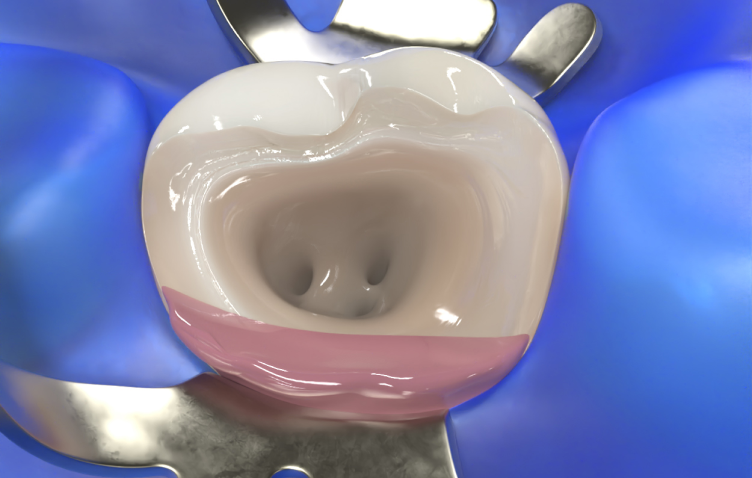

Halt für Kofferdam-Klammern

Nutzen Sie J-Temp als Halt für Kofferdam-Klammern und als Barriere für endodontische Spüllösungen.